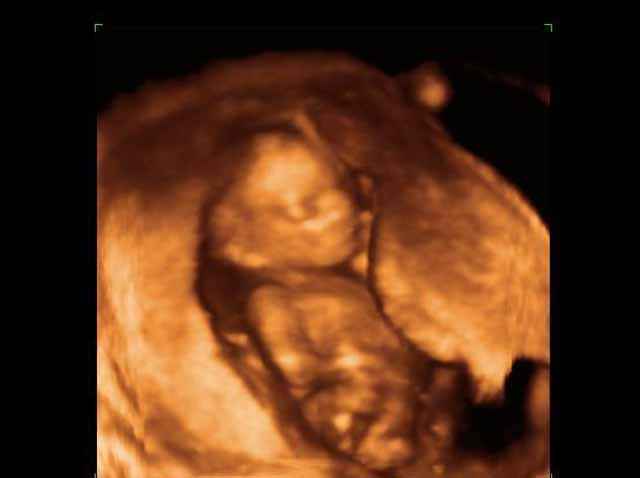

- 3D Fetal Profile Ultrasound Scan Photos

3D Second Trimester Ultrasound Scan Photos-second part of pregnancy | Dr N Layyous